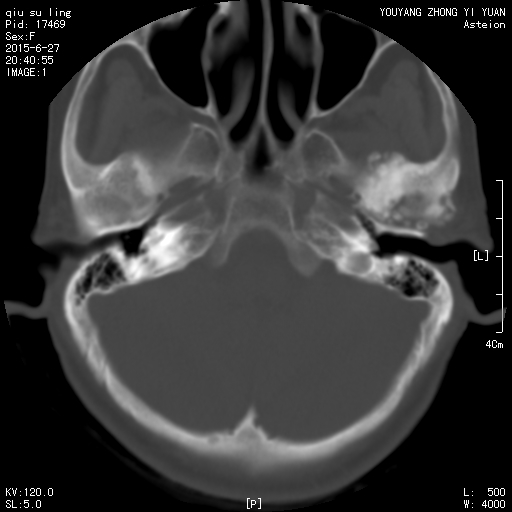

CT50750:急!!请老师们会诊一下寰枢椎是否有问题?

本帖最后由 cefcmj 于 2015-6-28 14:09 编辑 患者,女性,65岁。因打架颈椎疼痛。老师们你们看一下寰枢椎有半脱位吗?还有左侧下颌髁突周围多发米粒样高密度灶是什么? ...

1、寰枢椎未见异常。

2、左侧颞下颌关节滑膜骨软骨瘤病。

1、寰枢椎关节间隙左右不等考虑半脱位,建议结合临床。

从图片上看寰枢椎没有明显半脱位。